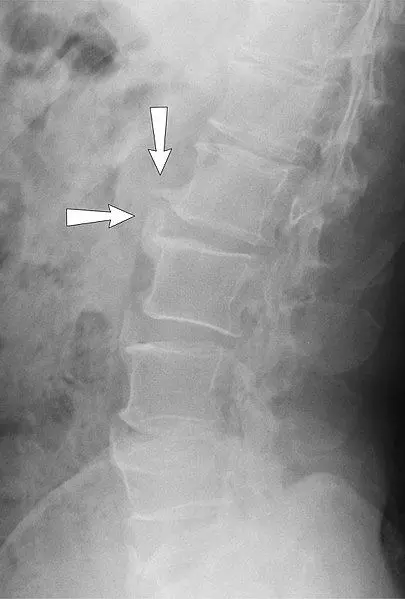

Spondylosis is the term used to describe chronic degenerative changes of the spine, including degeneration of the intervertebral discs and osteoarthritis of the facet joints, most commonly affecting the lumbar or cervical spine. It is usually caused by disc degeneration and marginal osteophytosis (bony spurs developing adjacent to the end plates of the disc).

It can present with radiculopathy causing dermatome/myotome symptoms. X-ray, MRI, and CT scans can be used in diagnosis but are not definitive alone. Treatment is conservative in nature and focuses on lifestyle modifications, pain management and physiotherapy.

Image - An X-ray showing the lateral view of lumbar spine spondylosis

Creative commons source by Nevit Dilmen and annotated by Mikael Häggström, M.D [CC BY-SA 4.0 (https://creativecommons.org/licenses/by-sa/4.0)]